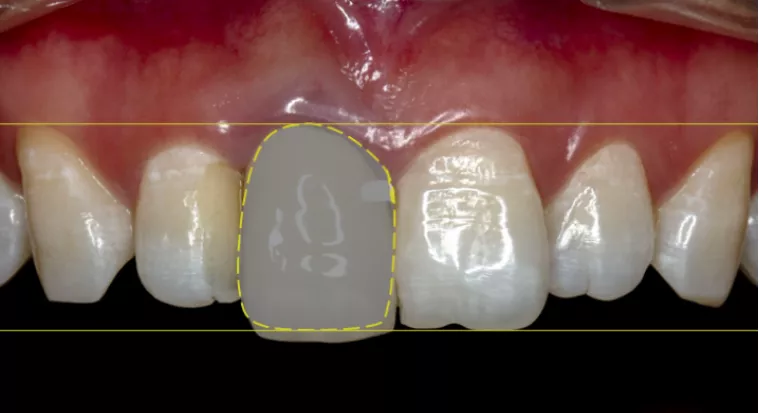

·      翻转21牙作为11牙理想修复体,获取11牙理想龈缘位置。

·      平移21牙釉牙骨质界至11牙,于CEJ下3mm处放置种植体。

·      Straumann® 骨水平锥柱状 (BLT) 种植体3.3mm*12mm;